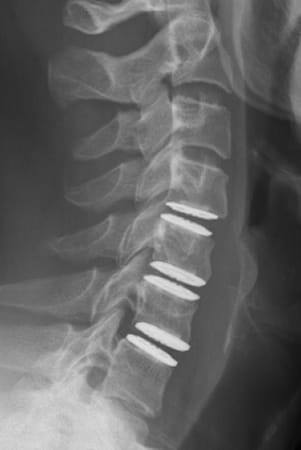

Auf diese Weise wird die Belastung der Wirbelsäule wie bei einer natürlichen Bandscheibe aufgenommen. Bei chronischen Bandscheibenerkrankungen sollte zuvor eine mindestens 3-monatige konservative Therapie versucht werden. Ist diese erfolglos oder treten nicht beherrschbare Schmerzen oder Nervenstörungen auf, so übernehmen die Krankenkassen in der Schweiz die Operation, sofern nicht mehr als zwei Bandscheiben betroffen sind und keine primäre Arthrose der Facettengelenke vorliegen. Bei akuten Bandscheibenvorfällen mit schweren Nervenstörungen oder Lähmungen besteht ebenfalls die Indikation zur Operation. Diese wird von vorne durch einen kleinen, etwa 2-3 cm langen, queren Hautschnitt in einer Hautfalte am Hals vorgenommen. Rechts oder links seitlich der Luft- und Speiseröhre gelangt man sehr schonend auf die Halswirbelsäule. Auf diese Weise kann die betroffene Bandscheibe vollständig entfernt werden und der Rückenmarkskanal sowie die entsprechenden Nervenwurzeln entlastet werden. Anschließend wird der Bandscheibenraum mit speziellen Instrumenten auf seine normale Höhe aufgedehnt, um die Nervenwurzeln zu dekomprimieren und Platz für die Prothese zu schaffen. Nach Ausmessen der passenden Größe und präziser Vorbereitung des Implantatbettes wird das Implantat unter Röntgenkontrolle eingesetzt. Beispiel einer degenerativen Bandscheibenerkrankung an der HWS und Versorgung mit drei visko-elastischen Bandscheibenprothesen

nach OP seitlich